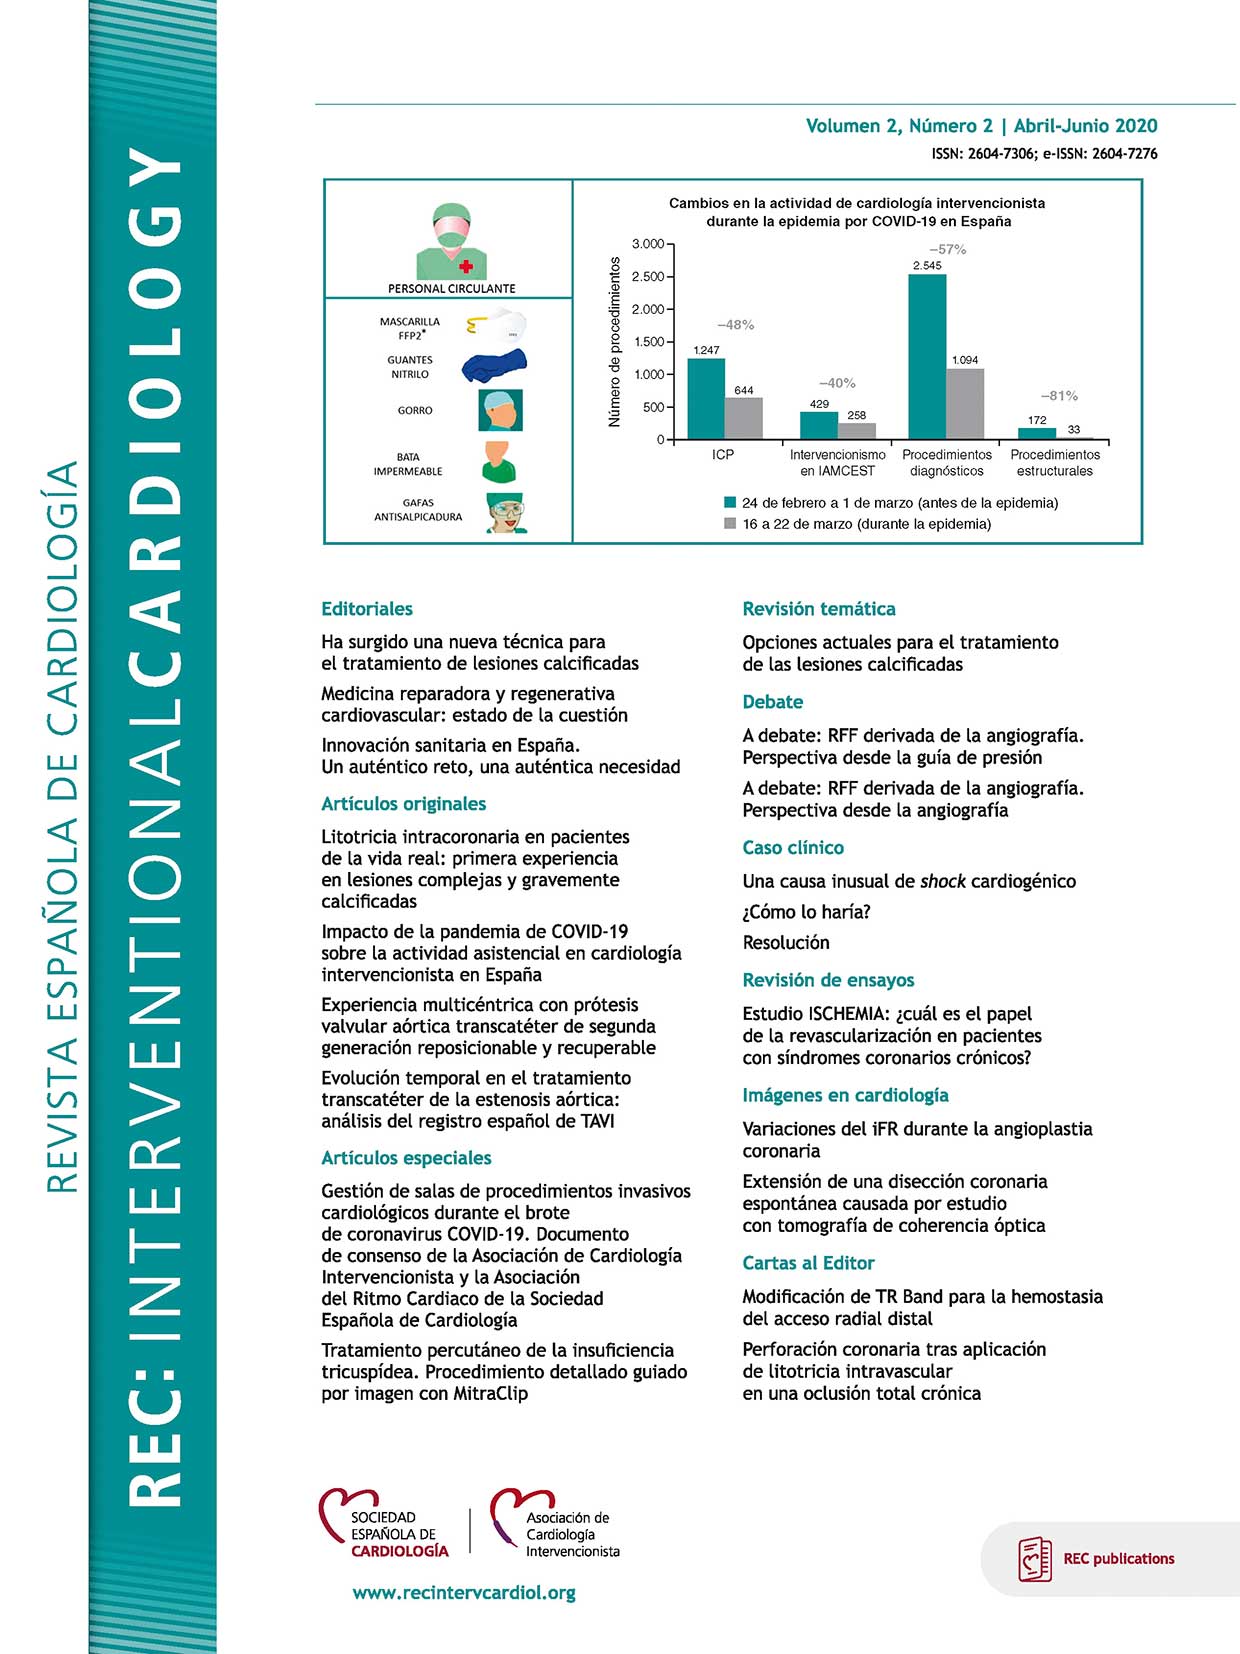

Impacto de la pandemia de COVID-19 sobre la actividad asistencial en cardiología intervencionista en España

REC Interv Cardiol. 2020;2:82-89